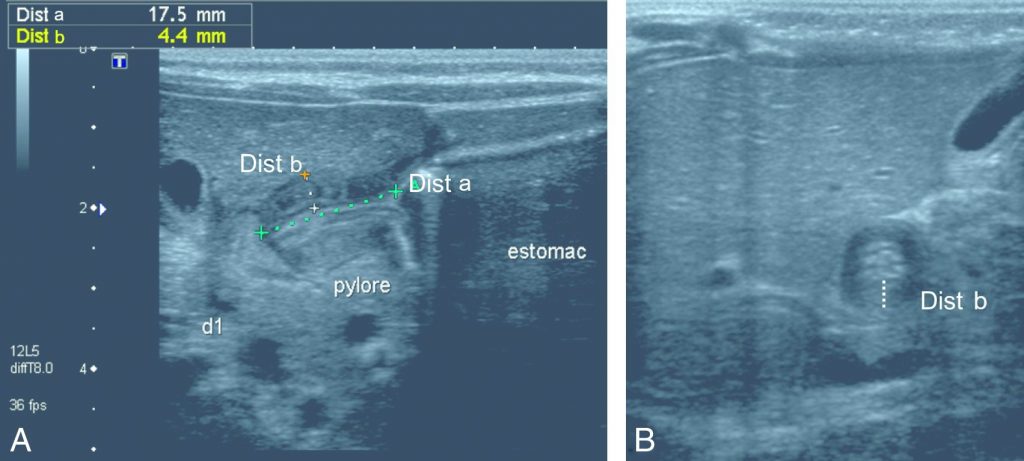

Le canal pylorique mesure normalement jusqu’à 10 mm, avec une épaisseur du muscle pylorique de 2 mm. Lors d’une sténose hypertrophique du pylore, il existe un allongement du canal pylorique et un épaississement musculaire. Si l’échographie met en évidence des mesures supérieures ou égales à 15 et 4 mm, le diagnostic de sténose hypertrophique du pylore est certain (figures 104.1 et 104.2).

Fig. 104.1. Échographie du pylore en coupes longitudinale (A) et transversale (B).

La musculeuse (Dist b) est épaissie, mesurée à 4,4 mm, et le canal pylorique (Dist a) est allongé, mesuré à 17,5 mm. Présence d’une importante stase gastrique. Sur le plan dynamique, il n’y a pas d’ouverture du canal pylorique lors de l’examen.

Source : CERF, CNEBMN, 2022.